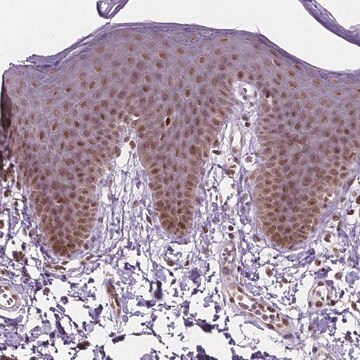

Anti-PER2 antibody produced in rabbit Prestige Antibodies® Powered by Atlas Antibodies, affinity isolated antibody, buffered aqueous glycerol solution